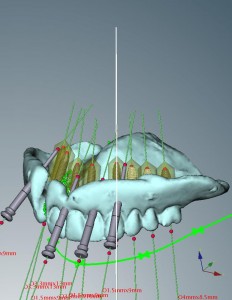

インプラントコンピュータシミュレーション。

インプラント治療を行う場合、全身状態やかみ合わせなどのお口の中の状態などの診査の他に、インプラントを入れる顎骨の状態を正確に知ることは、手術を成功に導くために最も重要な要因となります。

今から10年以上前は歯科用CTもまだあまり普及していませんでしたので、通常のレントゲンのみで手術を行っている時代もありました。

その後、CTにより3次元的に顎骨の状態を把握できるようになり、4~5年前まではただ診断に用いるのみでしたが、

現在ではCTで撮影した顎骨のデータを専用のソフト(ノーベルガイド)で解析し、手術用のガイドを製作出来るようになりました。

手術用のガイドを用いることにより、事前に診断し決定した位置や方向に、正確かつ早く、安全にインプラントを入れていくことが可能です。

インプラントは日々進歩しています。